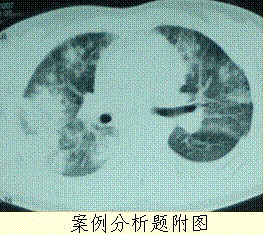

问题 患者女,23岁。间断发热伴皮疹1年半,诊断红斑狼疮。长期间断应用糖皮质激素治疗。近20 d高热(T 39℃)伴咳嗽咳痰, CT(附图)示双肺满布圆形密度增高阴影,大小不等,密度不均匀,上、中肺野分布较多,双侧少量胸腔积液。血常规:WBC 2.52×10/L, N 0.62, Hb 92 g/L;ESR 40 mm/h;痰真菌培养:烟曲霉3次阳性;支气管镜检查右下叶、左舌段见黄色黏液性血性分泌物,毛刷找到霉菌孢子。 治疗时,不考虑应用的药物是

选项 A.二性霉素B B.卡泊芬净 C.伏立康唑 D.氟康唑 E.伊曲康唑

答案 D